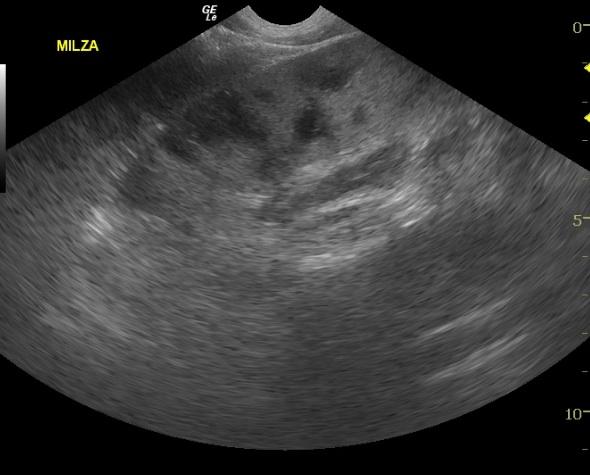

The spleen was heterogenous with mixed hypoechoic nodular or cavitated lesions and areas of capsular expansion. No evidence of rupture was noted. However, a mass is present at the caudal splenic body.

SplenicabcessSplenicabcessSplenicabcess